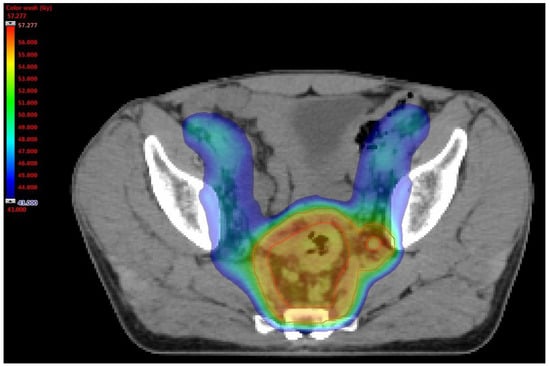

2.3. Neoadjuvant Treatment